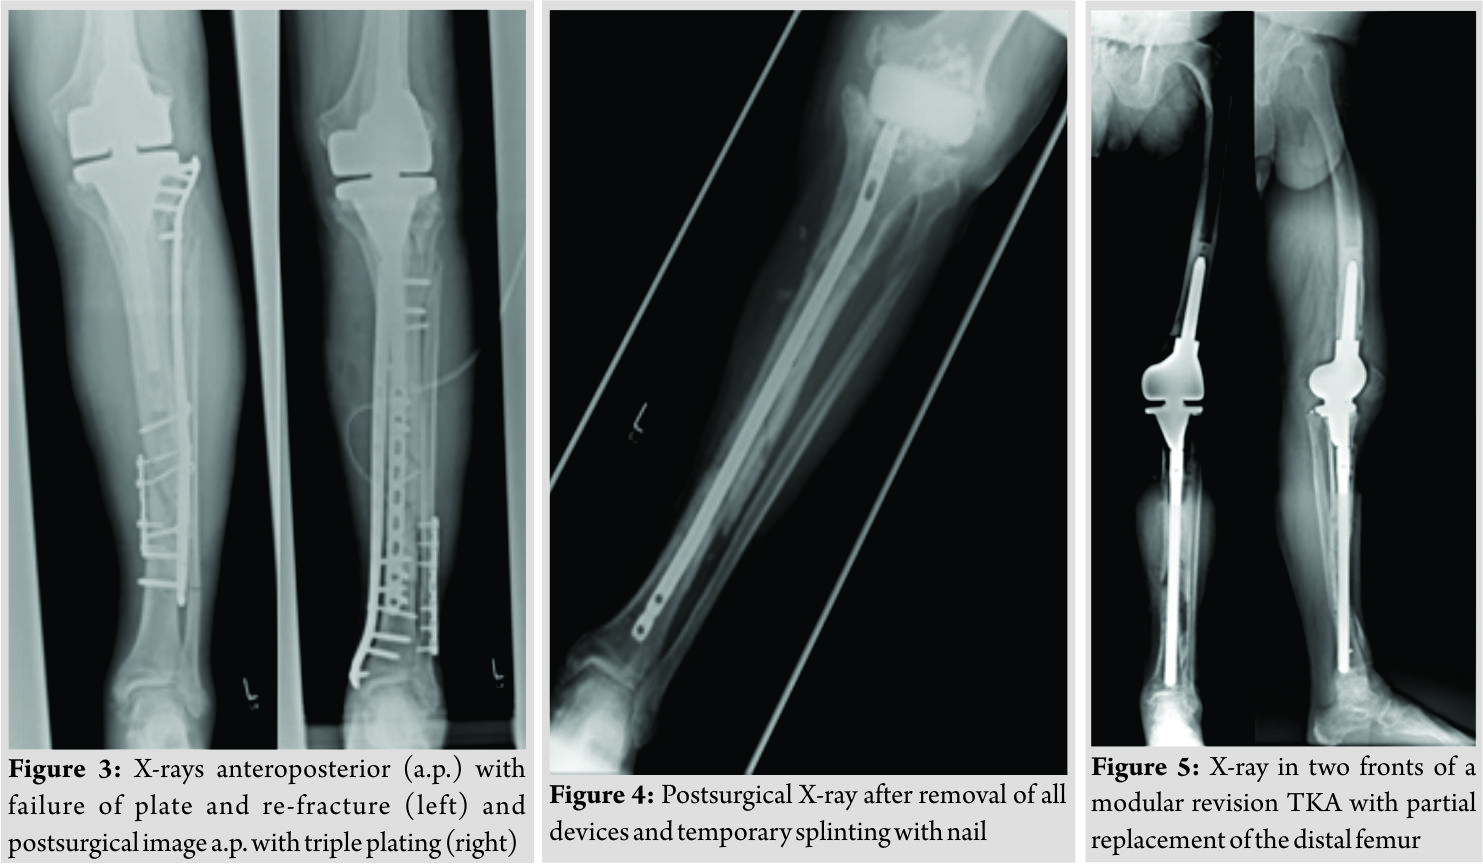

Inpatient care consisted of mobilization with two crutches and a partial weight bearing (20 kg). Microbiological examination of the initial joint puncture and all samples taking during the operation was negative. The patient was discharged with unremarkable wound conditions and normal blood counts. The patient was readmitted with persistent pain and serous secretion from a necrotic area of the distal wound 3months after discharge. Radiological examination showed a delayed union of the fracture. Immobilization in a cast and local resection of the necrosis could not prevent wound worsening within 1month. Therefore, revision surgery of the wound with a deep debridement had to be performed. Due to the missing wound consolidation, soft tissue debridement was performed in two more surgeries. The first procedure was completed with an extensive cleansing, insertion of a gentamicin-impregnated sponge, and an occlusive vacuum bandage. Antibiotic therapy was accomplished with a combination of cefuroxime (3 × 1.5 g i.v., Fresenius Kabi Austria GmbH, Graz, Austria) and clindamycin (2 × 600 mg, MIP Pharma GmbH, Blieskastel, Germany). This therapy was given in accordance with the spectrum of resistance of a multi-sensitive Staphylococcus aureus and Enterobacter cloacae (wound sample) and S. aureus, Finegoldia magna, and Corynebacterium xerosis (fracture site samples). As there was no tendency toward healing, a further surgery with new lateral and medial plating was performed. The distal wound lesion was covered with a MESH graft. Post surgical therapy included mobilization with full weight bearing. In addition, osteoanabolic therapy with Teriparatide (250 µg/ml, Lilly Germany GmbH, Bad Homburg) to improve fracture healing was applied. Antibiotic treatment was continued for 6 weeks. Histological examination confirmed an underlying chronic bone infection and the nonunion. The blood counts were normal when the patient was discharged after 27 days. 2 weeks after hospital discharge, the patient reported a sudden, atraumatic pain with immobilization. X-rays documented a fracture dislocation with the failure of the medial and lateral device and, in addition to these findings, a new distal fracture of the fibula (Fig. 3). There were no signs of consolidation at the former fracture site, and revision surgery was necessary. With the exception of two broken screw bodies, all devices were removed. A triple-plate reosteosynthesis was performed, including a 14-hole inverse LISS plate on the medial side, a 12-hole limited contact dynamic compression (LCDC) plate at the dorsal tibia aspect, and a 7-hole reconstruction plate at the new distal fibula fracture (all devices, Synthes GmBH, Umkirchbei Freiburg, Germany, Fig. 3). The nonunion was resected,and the lesion was filled with an equilateral autologous spongiosa graft of the femur taken by a reamer-irrigator-aspirator system. A multidrug-resistant Staphylococcus epidermidis (MRSE) was isolated from the microbiological samples. Since the MRSE had also been isolated during prior surgeries, it was considered a major pathogen; therefore, antibiotic treatment with cefuroxime and clindamycin was changed to vancomycin (2 × 1 g, MIP Pharma GmbH, Blieskastel, Germany) and rifampicin (2 x 600 mg, Riemser Pharma GmbH, Greifswald, Germany). The patient was discharged with an oral combination of linezolid (2 × 600 mg, MIP Pharma GmbH, Blieskastel, Germany) and rifampicin (2 × 600 mg, Riemser Pharma GmbH, Greifswald, Germany) for additional 4weeks. Blood values were taken frequently, revealing normal WBC counts and regressive CRP values. A follow-up was planned at our outpatient clinic at the end of the period of unloaded mobilization 8weeks after surgery. The initial follow-up and subjective outcome were satisfactory at 8weeks postoperatively. There was no evidence of a persistent infection. The patient had completed 2months of mobilization without weight bearing and had started partial weight bearing without any problems a few days before. Therefore, slowly increasing weight bearing to improve inpatient rehabilitation and functional outcome of the affected limb was recommended. The patient was readmitted from rehabilitation to our department in January 2015 due to a progression of knee pain and moderately elevated paraclinical values of infection. Examination at admission showed normal wounds at the fracture site, but at the knee, the skin was irritated and swollen. X-rays showed a small amount of new bone formation at the medial and lateral side of the former tibial fracture, but a fracture union was still not present. A knee puncture was performed, and the microbiological assessment showed a known MRSE, previously of the fracture site, now with a limited spectrum of sensitivity. A bone and leukocyte scintigraphy showed a persistent (infectious) nonunion and aseptic loosening of the TKA due to ascending infection. With the additional septic focus, there was a need for complete removal of all implants. Therefore, a two-stage implant change was planned. After removal of all implants, a deep debridement was performed,and a hand-formed bone cement knee spacer including antibiotics (Copal G+C 1 × 40 mg, Heraeus Medical GmbH, Wehrheim, Germany) was implanted. Microbiological and histological samples taken during surgery confirmed the chronic bone infection and septic TKA. An antibiotic treatment was started perioperatively and was given for 6weeks with a combination of vancomycin (2 × 1 g, MIP Pharma GmbH, Blieskastel, Germany) and rifampicin (2 × 600 mg, Riemser Pharma GmbH, Greifswald, Germany) followed by an oral mono-therapy with linezolid (2 × 600 mg, PHARMACIA GmbH, Karlsruhe, Germany). The mobilization was performed with full weight bearing using an individual constructed lower limb load-relieving orthosis by Allgöwer. After an antibiotic-free interval of 2 weeks, the patient was admitted for a diagnostic joint puncture. However, the knee puncture again showed purulent synovial fluid with the isolation of the prior known MRSE. The remaining broken screws and a bone abscess close to the former nonunion was removed within revision surgery. A tibial nail (T2, 315 × 10 mm, Stryker Trauma GmbH, Schönkirchen, Germany) was used for temporary intramedullary splinting and to provide further consolidation of the circumferential callus bone. Furthermore, a new bone cement spacer (Palacos R+G, 2× 40 mg, Heraeus Medical GmbH, Wehrheim, Germany) with two additional antibiotic-impregnated chains (2 × 30, Biomet Deutschland GmbH, Berlin, Germany) was implanted (Fig. 4). MRSE was ascertained everywhere except for the distal femur. In accordance with the pathogen’s spectrum of resistance, a new 6-week course of therapy with vancomycin (2 × 1 g, MIP Pharma GmbH, Blieskastel, Germany) was begun and switched to oraltherapy with linezolid (2 × 600 mg, PHARMACIA GmbH, Karlsruhe, Germany) only. The previous mobilization using the orthesis was continued. In August 2015, a puncture of the knee joint after an antibiotic-free interval showed no pathogens. Clinical examination was without any signs of persistent infection. X-rays showed only a partial consolidation of the fracture at the tibia, but the fibula was consolidated. Therefore, reimplantation of a special revision TKA, also addressing the tibial fracture was scheduled. Revision surgery included removing the nail and all other foreign bodies and an extensive debridement with reaming of the intramedullary cavity of the tibia. The surgery was completed by a partial replacement of the distal femur due to bone loss and a modular revision TKA was implanted (Mega C, modular tibia with a 14/280 mm cementless tibia stem, modular femur condyle with a 16/100 mm cemented stem, Waldemar Link GmbH and Co. KG, Hamburg, Germany; Fig. 5). The tibial fracture site was splinted stable with the long cementless stem by the means of a press fit. Intraoperative range of motion of the knee joint was extension/flexion of 0/0/100. The patient underwent full weight bearing using two crutches and patient’s orthosis for 8weeks postoperatively. Post-operative X-rays showed no malalignment of the TKA and good fracture stabilization by the tibial stem. Laboratory counts and infectious values normalized, and there was a remarkable improvement in the patient’s quality of life. A new rehabilitation was scheduled after the inpatient time of 3weeks. The patient was discharged with an active ROM of 90° in flexion. He was able to exercise on an even track for more than 20 min. The patient underwent 4months of follow-up after successfully completing rehabilitation. The patient was able to walk under full weight bearing with the aid of two crutches. Occasionally, the orthosis is carried for long distances. He reported an intermittent pain at the superficial goose’s foot in cases of higher stress. There was a temporary relief after a local anesthetic infiltration, but the pain, in general, was described as moderate. All wounds were dry and without any signs of infection. The active range of motion was tested with flexion of 0/0/90°. The patient was seen for the last follow-up 15 months after revision TKA with only moderate pain at the medial knee site. Mobilization was performed with the use of one crutch, and knee flexion is limited to 80°, which is described as acceptable for patient’s daily activities. The patient is confident with the functional outcome and quality of life.